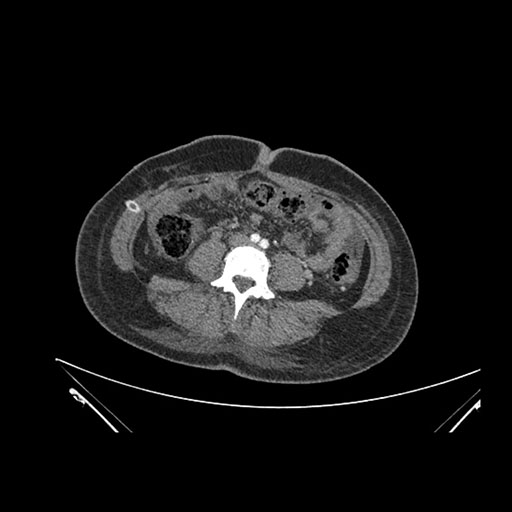

Imaging Analysis

Look through the patient's CT scan to identify any areas of concern for the necessary procedure.

Axial Arterial

Based on initial findings, which issue(s) would you be most concerned about?